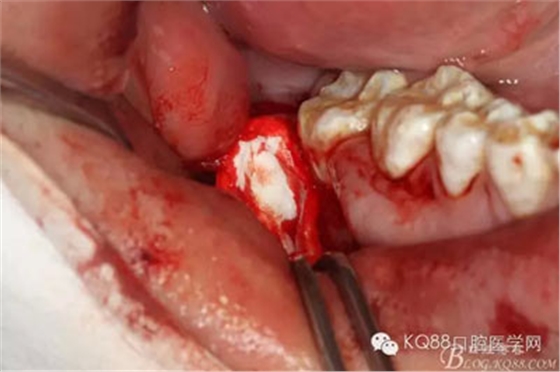

圖9.不斷的耐心去骨,發(fā)現(xiàn)48被下方的囊性改變趕到舌側(cè)。

圖10 開(kāi)始分牙,術(shù)中分牙經(jīng)歷非??部溃@頭操作異常困難,因?yàn)?8倍囊性改變推至舌側(cè)。

圖13.把48干掉,繼續(xù)戰(zhàn)斗,摘除下方囊腫,結(jié)果翻瓣超過(guò)前庭溝時(shí),發(fā)現(xiàn)頰側(cè)骨板缺失,與48牙槽窩完全貫通

注意看:骨間隔上方是48牙槽窩,下方是囊腔。有點(diǎn)后悔翻瓣有點(diǎn)過(guò)淺了。